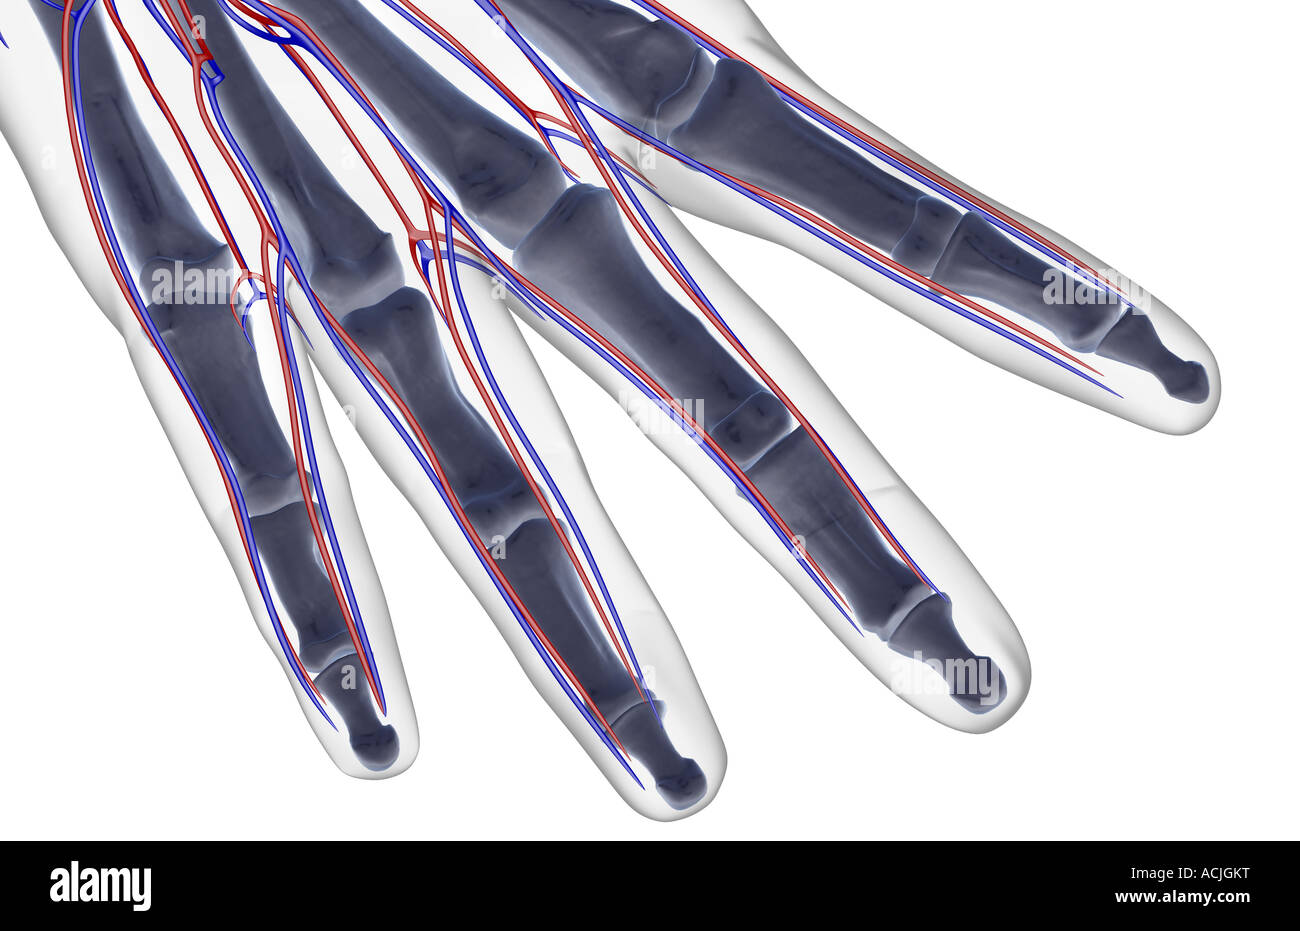

The blood supply of the fingers Stock Photohttps://www.alamy.com/image-license-details/?v=1https://www.alamy.com/stock-photo-the-blood-supply-of-the-fingers-13170539.html

The blood supply of the fingers Stock Photohttps://www.alamy.com/image-license-details/?v=1https://www.alamy.com/stock-photo-the-blood-supply-of-the-fingers-13170539.htmlRFACJGKT–The blood supply of the fingers